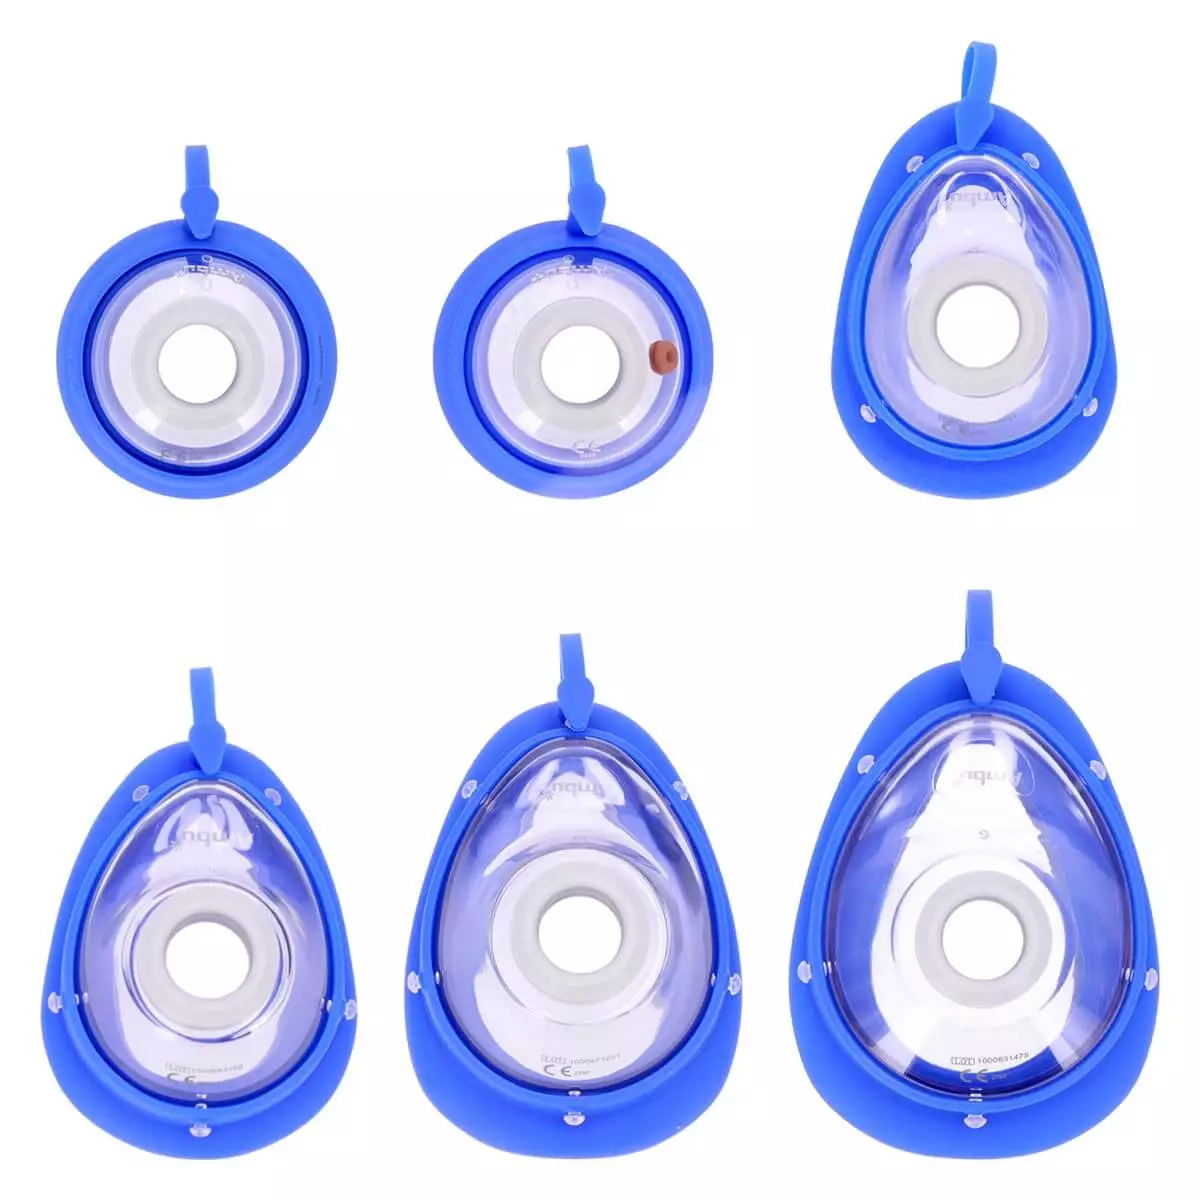

Haal diep adem: het DocCheck "Luft" beademingsmasker voor de tas voorkomt direct contact met de lippen tijdens mond-op-mondbeademing in een noodgeval en vermindert de inhibitie om onmiddellijk eerste hulp te verlenen. Plaats het masker gewoon over de mond en neus van het slachtoffer. Het anatomisch gevormde luchtkussen past goed op het gezicht en de elastische band houdt het masker stevig op zijn plaats. Het meegeleverde bacteriefilter voorkomt contact met lichaamsvloeistoffen van het slachtoffer en voorkomt infecties.

- Beademingsmasker met luchtkussen en elastische rubberen band voor beademing van volwassenen, kinderen en zuigelingen

- Zorgt voor een fysieke barrière tussen hulpverlener en patiënt

- Met eenrichtingsventiel en filter voor maximale hygiëne

- Extra verbindingsstuk voor zuurstoftoediening

- Afmetingen (masker): L 12,5 x B 10 x H 3 cm